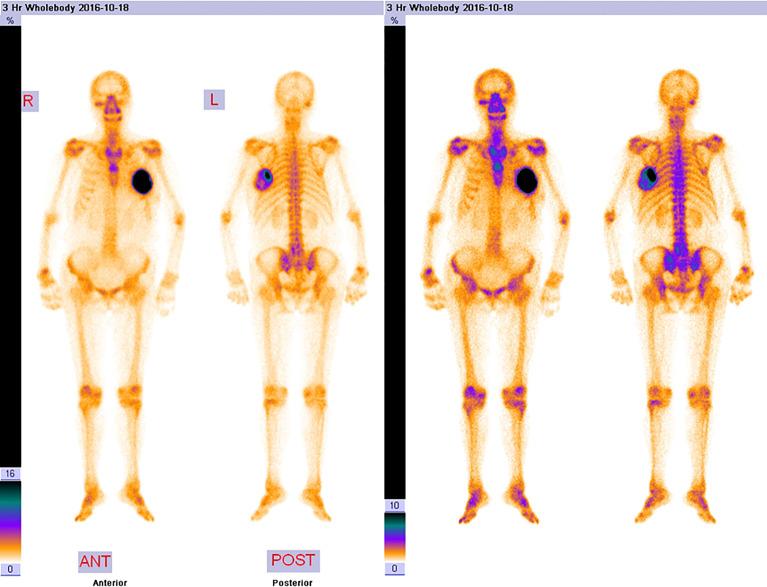

An 83-year-old Chinese woman went to our hospital because of a palpable mass she had had for 8 months in the left breast accompanied by persistent dull pain for 10 days. This mass was initially misdiagnosed as a degenerating fibroadenoma and was graded as probably benign (BI-RADS category 3) by ultrasonography (US) and computed tomography (CT) plain scan and contrast enhancement of chest. Eight months later, it was presumed to be highly malignant and graded as BI-RADS category 4C because of its rapid growth and more calcifications by US and CT. 99mTc-MDP whole-body bone imaging showed that there was a mass-like abnormal radioactive concentration of Tc-99m outside the bone of the left chest. The lumpectomy of the left breast was indicated, and the pathological findings were POB. She succumbed to respiratory failure caused by multiple lung metastases 4 months after the operation.

一名83岁中国女性因左乳可触及肿块8个月且伴有持续钝痛10天前来我院就诊。该肿块最初被误诊为退变的纤维腺瘤,经超声(US)、胸部计算机断层扫描(CT)平扫及增强扫描后被分级为可能良性(BI-RADS 3类)。8个月后,因其生长迅速且经超声和CT显示有更多钙化,被推测为高度恶性,分级为BI-RADS 4C类。99mTc-MDP全身骨显像显示左胸壁外有一肿块样异常放射性锝-99m浓聚。遂行左乳肿块切除术,病理结果为POB。术后4个月,患者因多发肺转移导致呼吸衰竭死亡。